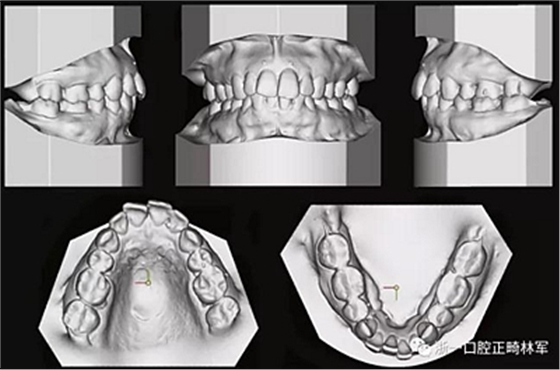

由于下頜中切牙間沒有間隙行下頜正中切開術(shù),故進行術(shù)前正畸擴展間隙。下頜前牙粘托槽,中切牙托槽成交放置,將中切牙牙根分開。使用0.018X0.018鎳鈦絲及置于下頜左、右中切牙之間的推簧推間隙。3個月后拍攝CBCT示已有足夠間隙行下頜正中截骨術(shù)。

手術(shù)前三周,上、下頜磨牙和前磨牙使用分壓圈進行分牙。術(shù)前一天,去除下頜切牙托槽,安裝hyrax擴弓器。

全麻下進行上頜骨腭中縫骨皮質(zhì)劈開及下頜正中劈開術(shù)。手術(shù)后,用X光片檢查上頜骨和下頜骨中線切口的位置和方向。

術(shù)后第9天開始旋轉(zhuǎn)擴弓器,每天轉(zhuǎn)2次,每次轉(zhuǎn)90度,即擴開0.5mm。每隔1周進行檢查,目標上頜擴開9mm,下頜擴開6mm。18天后,上頜中切牙間出現(xiàn)8mm間隙。下頜出現(xiàn)6mm間隙,(于13天出現(xiàn)后,停止旋轉(zhuǎn)擴弓器)。在擴弓器旋轉(zhuǎn)3天后,拍片發(fā)現(xiàn)左下頜中切牙遠中牙根中段有一條低密度陰影,臨床冷熱診反應(yīng)遲鈍,可能為術(shù)中損傷所致。牙體牙髓科會診,建議行根管治療,故行根管治療。